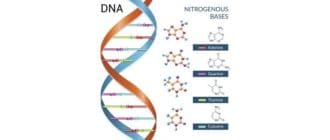

DNAはおそらく最も有名な生体分子です。それは地球上のすべての形の人生に存在します。 DNAやデオキシリボ核酸は何ですか?ここでは、必要不可欠なものについて説明します。 実質的にあなたの体内のすべての細胞にはDNAや遺伝 […]